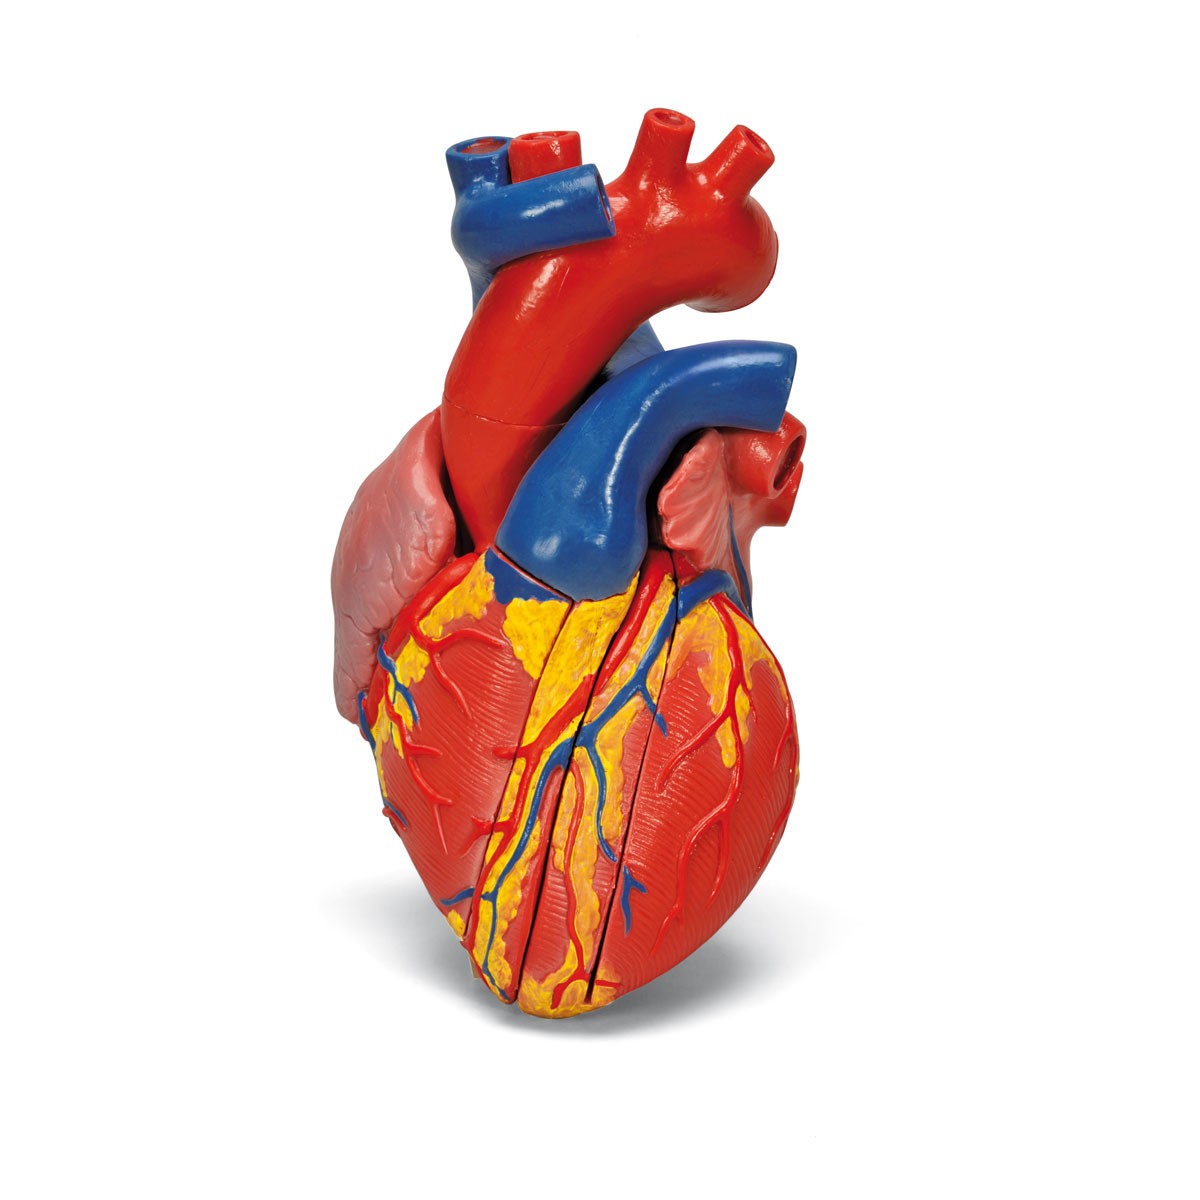

Фотографии и 3D-модели анатомии сердца человека